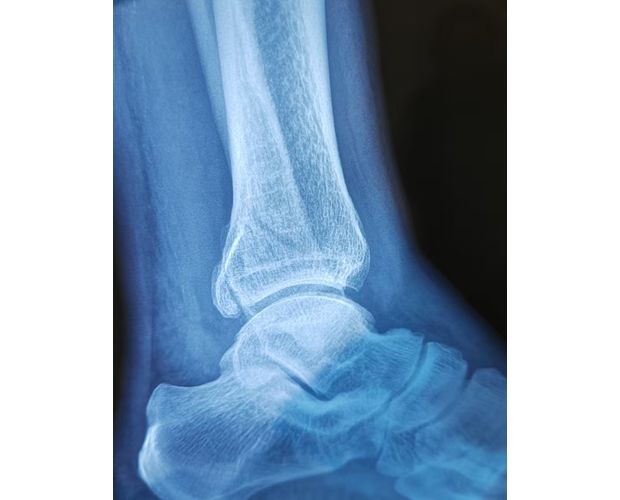

2月4日,何店镇中心卫生院接诊一名左踝关节外伤患者,经影像检查,确诊为左胫、腓骨下段骨折。外科医生姜稳迅速完成术前检查及病情评估,并与患者及家属深入沟通治疗方案。在患者强烈要求于本院进行手术的情况下,为最大限度保障手术质量与安全,该院特邀请医共体牵头单位——曾都区人民医院脊柱创伤外科专家团队前来指导。